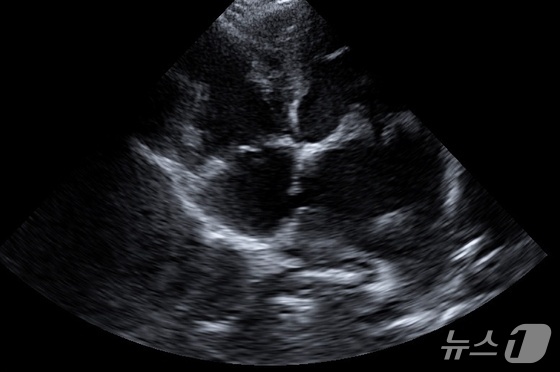

심장 초음파 검사 결과, 사랑이는 기존 MMVD로 인해 좌심방 압력이 극도로 상승된 상태였다. 이 과정에서 좌심방과 우심방을 나누는 심방중격 부위가 과도한 압력을 견디지 못하고 터져 있었다.

사랑이는 선천적인 심장 기형은 아니었다. 주치의는 오랜 시간 누적된 심장 부담으로 인해 후천적으로 발생한 심방중격 파열로 판단했다.

강아지 초음파 검사 결과 심방중격 부위가 터진 모습(더케어동물의료센터 제공) © 뉴스1